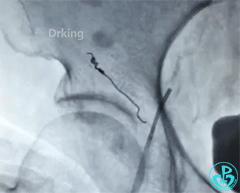

我们用弹簧圈来封堵。一个不行就两个。终于堵住血管!

预后:无再出血,无不良主诉,已出院。